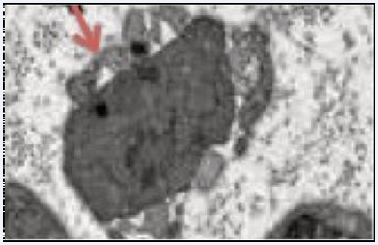

This local axonal process consists of dedifferentiating mature Schwann cells into specialized repair cells called Büngner cells [19] (Figure 4).

Figure 4 Small regenerative axonal buds (asterisk) and adjacent Büngner cells are typical tissue components of an injured peripheral nerve.

This involves an activation state and a new degree of cellular plasticity, representing a new cell type specialized in regenerating peripheral nerves by creating pathways that guide the axon to its target [20] by regeneration tracks called Büngner bands [21] (Figure 5).